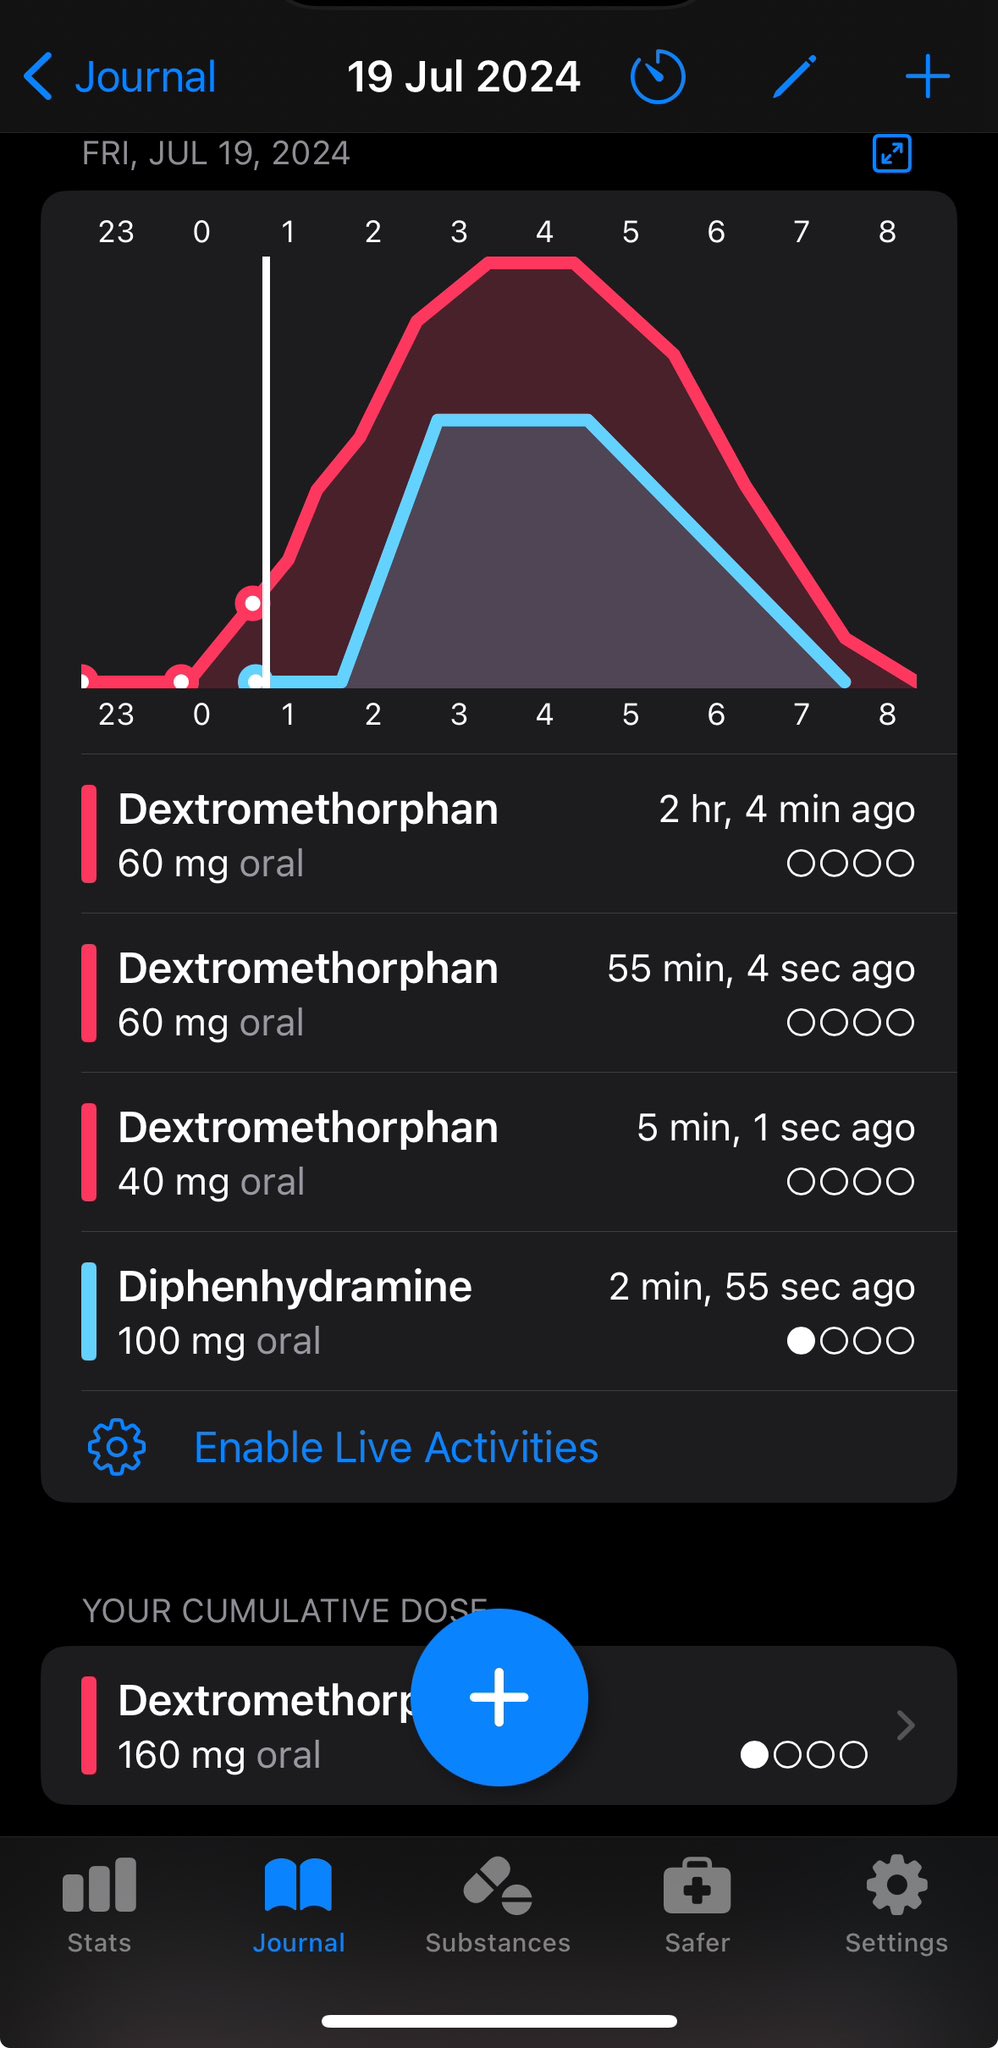

今天起来特别晕,完全不知道是怎么回事,以为是昨天测试物质的副作用我在想这么恐怖,然后怀疑今天是不是丁螺环酮吃了两次,直到我去看用药记录。。

好家伙唑吡坦又骗我吃药了还顺带上了个失忆状态,这下子知道是谁干的了。吃auv之后dxm清除得特别慢...让我感觉要从此告别了的程度,加上我基因检测本来cyp2d6就是中速代谢,这个尾巴就被拖的特别长